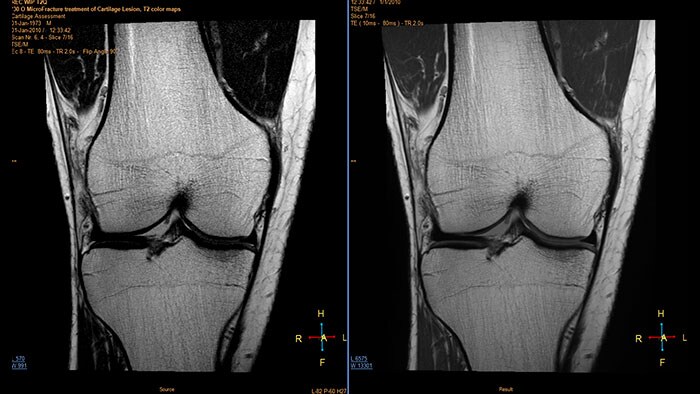

Improving clinical confidence and productivity with advanced MRI applications. Explore Philips magnetic resonance imaging applications for different clinical areas.

Fast and high-quality imaging, powered by AI

Achieve up to 3 times faster¹ MRI scanning while enhancing image quality with SmartSpeed AI. Philips SmartSpeed delivers both exceptional image quality and speed without compromise, powered by award-winning AI technology² and a state-of-the-art Compressed SENSE speed engine.

Quantitative MR imaging with AI technology

Smart Quant Neuro, a combination of AI reconstruction technology and quantitative MR, is designed to allow you to perform fast and high-quality MR imaging of neuro with a single quantification scan to increase your diagnostic confidence.